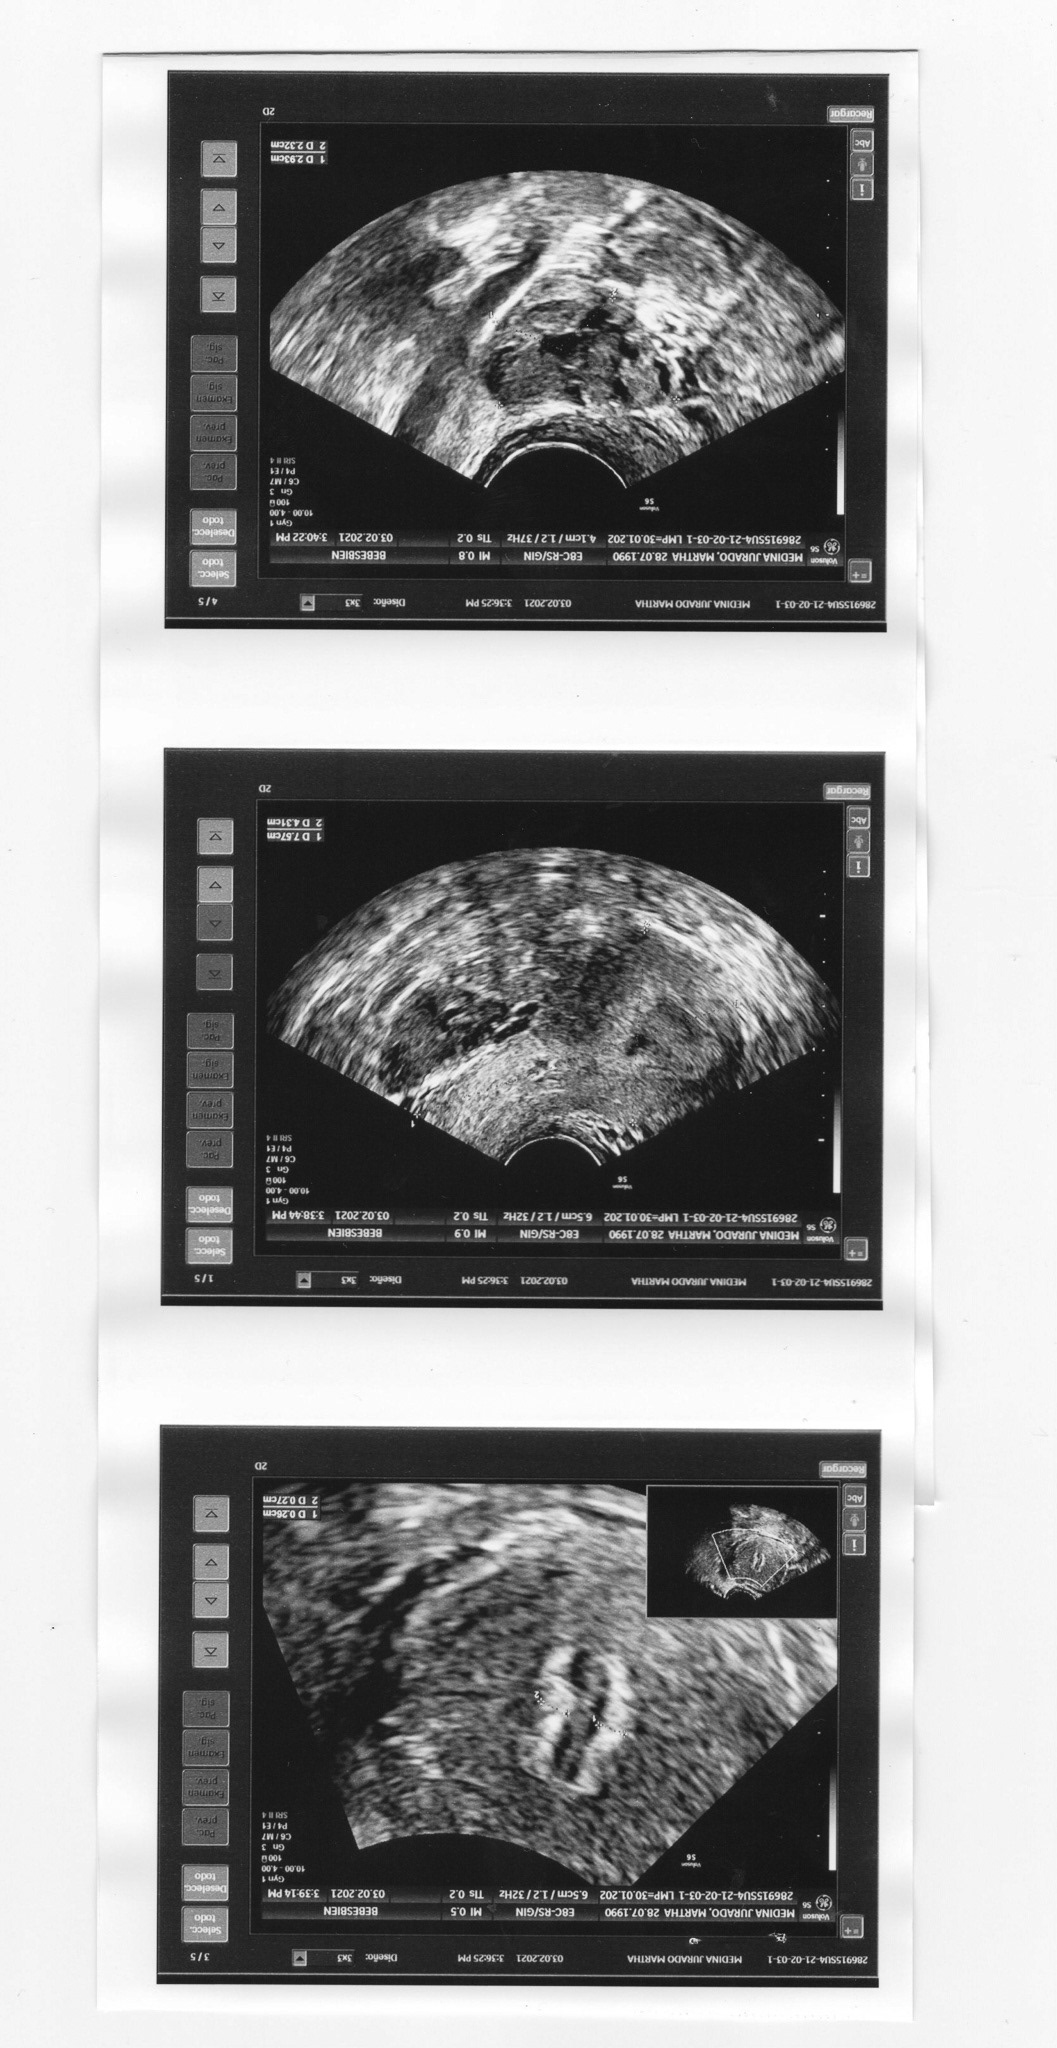

Es una metáfora de la luz que nace en medio de la oscuridad: revela y denuncia. Este proyecto surge a partir de un proceso de acompañamiento emocional tras ser diagnosticada con Virus del Papiloma Humano (VPH) de alto riesgo, uno de los principales factores que desencadenan el cáncer cervicouterino. Desde mi experiencia, reflexiono sobre los factores que atraviesan la salud sexual femenina; la falta de información, el miedo, la culpa y la vergüenza, un sistema educativo lleno de prejuicios, influenciado por la religión católica y repetido en los discursos institucionales, además de la falta de recursos económicos y las barreras para acceder a la salud pública. Busco abrir la conversación sobre el VPH, crear redes de apoyo y generar puentes que permitan dialogar sobre la salud sexual con perspectiva de género.